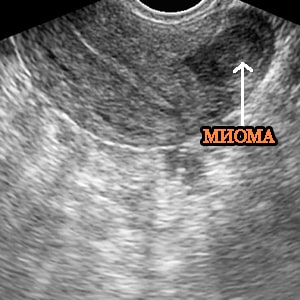

миома на УЗИЧто такое миома?

• Трансвагинальное УЗИ ( ультразвуковое исследование).